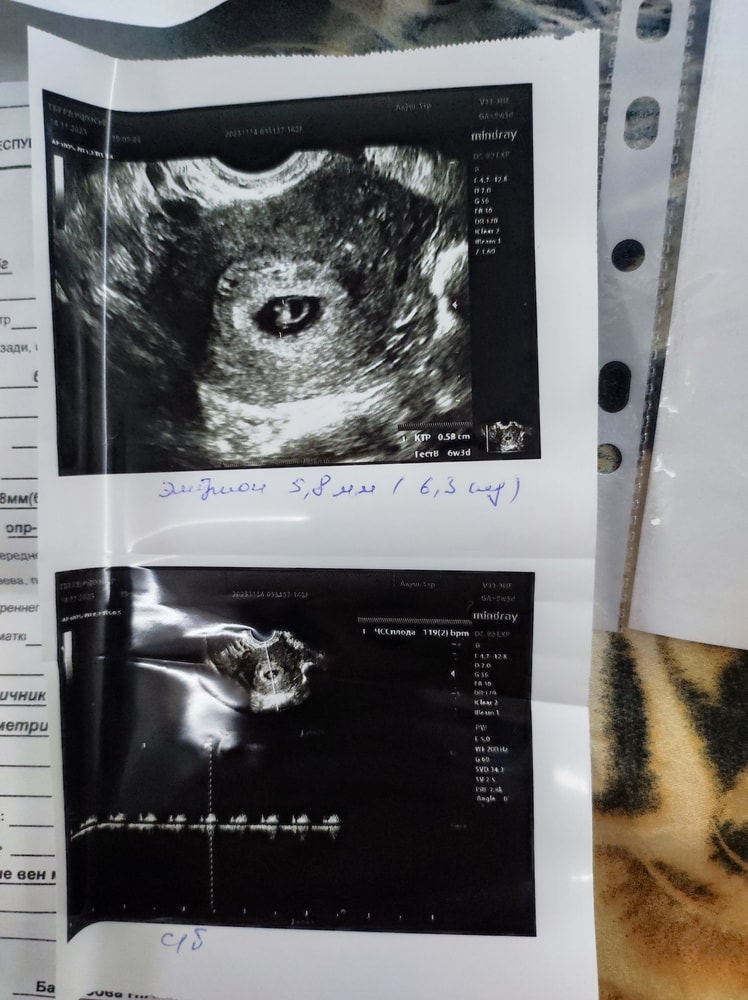

Метод Рамзи) погадаем ?😀

Изображение

Таня, Изображение